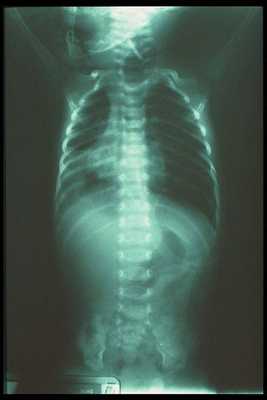

(Слева) Новорожденный мужского пола с атрезией анального отверстия. В данном случае половые органы сформированы нормально, но по данным УЗИ есть подозрение на аномалии позвоночника.

(Справа) Рентгенография, выполненная у этого же новорожденного в прямой проекции, позволяет увидеть многочисленные дефекты позвонков пояснично-крестцового отдела. Аномалии дистальных отделов позвонков часто видны в сочетании с аномалиями анального отверстия и прямой кишки и служат важной частью ассоциации VATER/VACTERL.